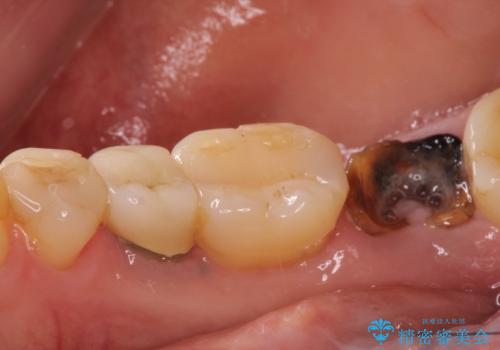

- 右下の奥歯をかぶせ物がとれたまま放置しているところに歯を入れたいとのことで来院されました。

精査すると保存が難しいため抜歯をして、インプラントを埋入、かぶせ物を装着する計画としました。